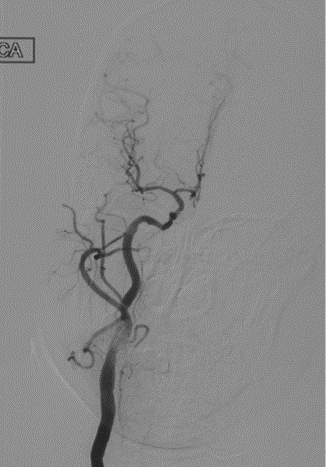

辅助检查(DSA)

主动脉弓+L-CA

波科支架怎么样径技-弓上病例大赏|第210期·右侧颈内动脉球囊扩张术+支架植入术_https://www.jmylbn.com_新闻资讯_第11张

R-CA

波科支架怎么样径技-弓上病例大赏|第210期·右侧颈内动脉球囊扩张术+支架植入术_https://www.jmylbn.com_新闻资讯_第12张